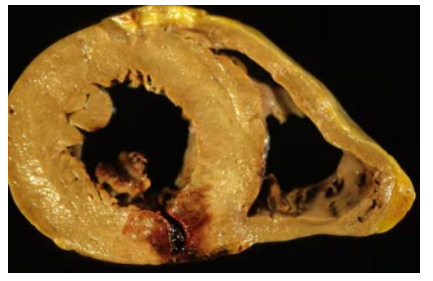

myocardial infract (early stages)

Mycardial infract

Myocardial infract early stages

Myocardial infract

green = early infract